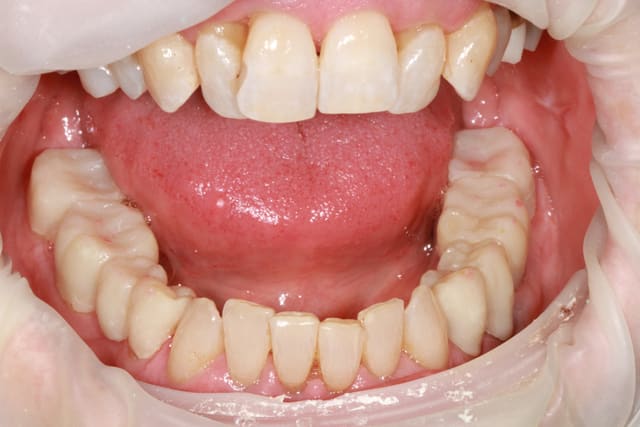

patiente 62 ans région Parisienne, appelle pour un avis, son praticien, paro, imlpanto etc... lui dit que sa paro n'a plus besoin de soin et propose pour les 6 antérieurs (j'ai le devis sous les yeux) 6 Inlay Core et 6 CCM...

Les panos sont du départ, les photos sont après un nettoyage ...profond et soins.